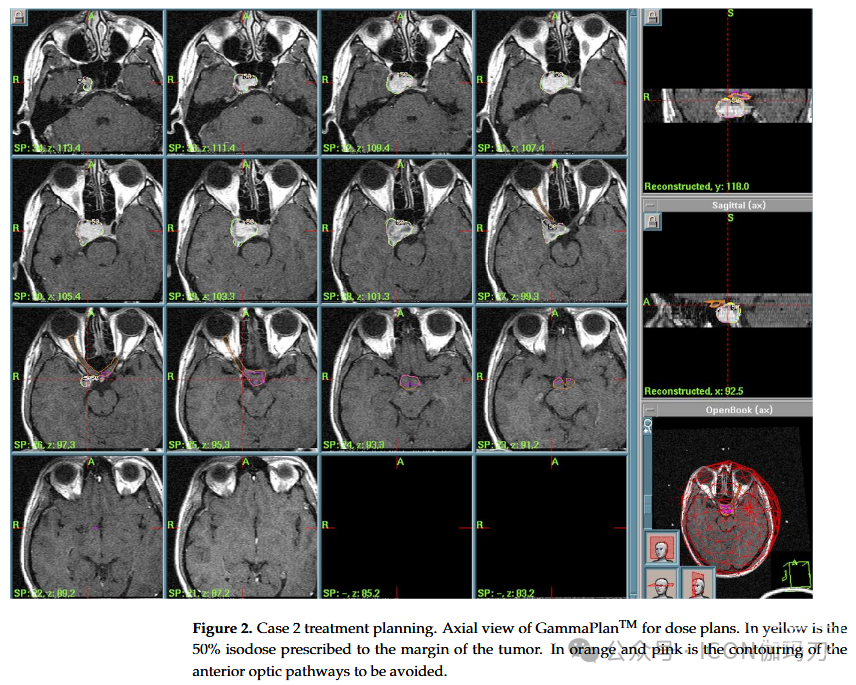

病例2:24岁男性,复视病史6个月,既往诊断为下丘脑错构瘤,累及右侧海绵窦。在另一个中心进行显微手术(双额开颅)后,组织学上证实了诊断。临时诊断后,手术中断,建议放射外科治疗。考虑到具有挑战性的位置和并发症的风险,在多学科讨论后选择了辅助GKRS治疗。治疗参数(2005年)如下:PI为50%,PD为13.5 Gy, MD为27 Gy,总剂量为95.2 mJ, 12 Gy体积为7.13 cc(图2)。患者治疗当日出院,无新的神经功能障碍。经过5年良好的临床和放射影像学随访,患者失访(no longer contactable)。

图2。病例2治疗方案。GammaPlanTM轴向视图的剂量计划。黄色部分为肿瘤边缘的50%等剂量线。橙色和粉色是要避免的前部视神经的轮廓。